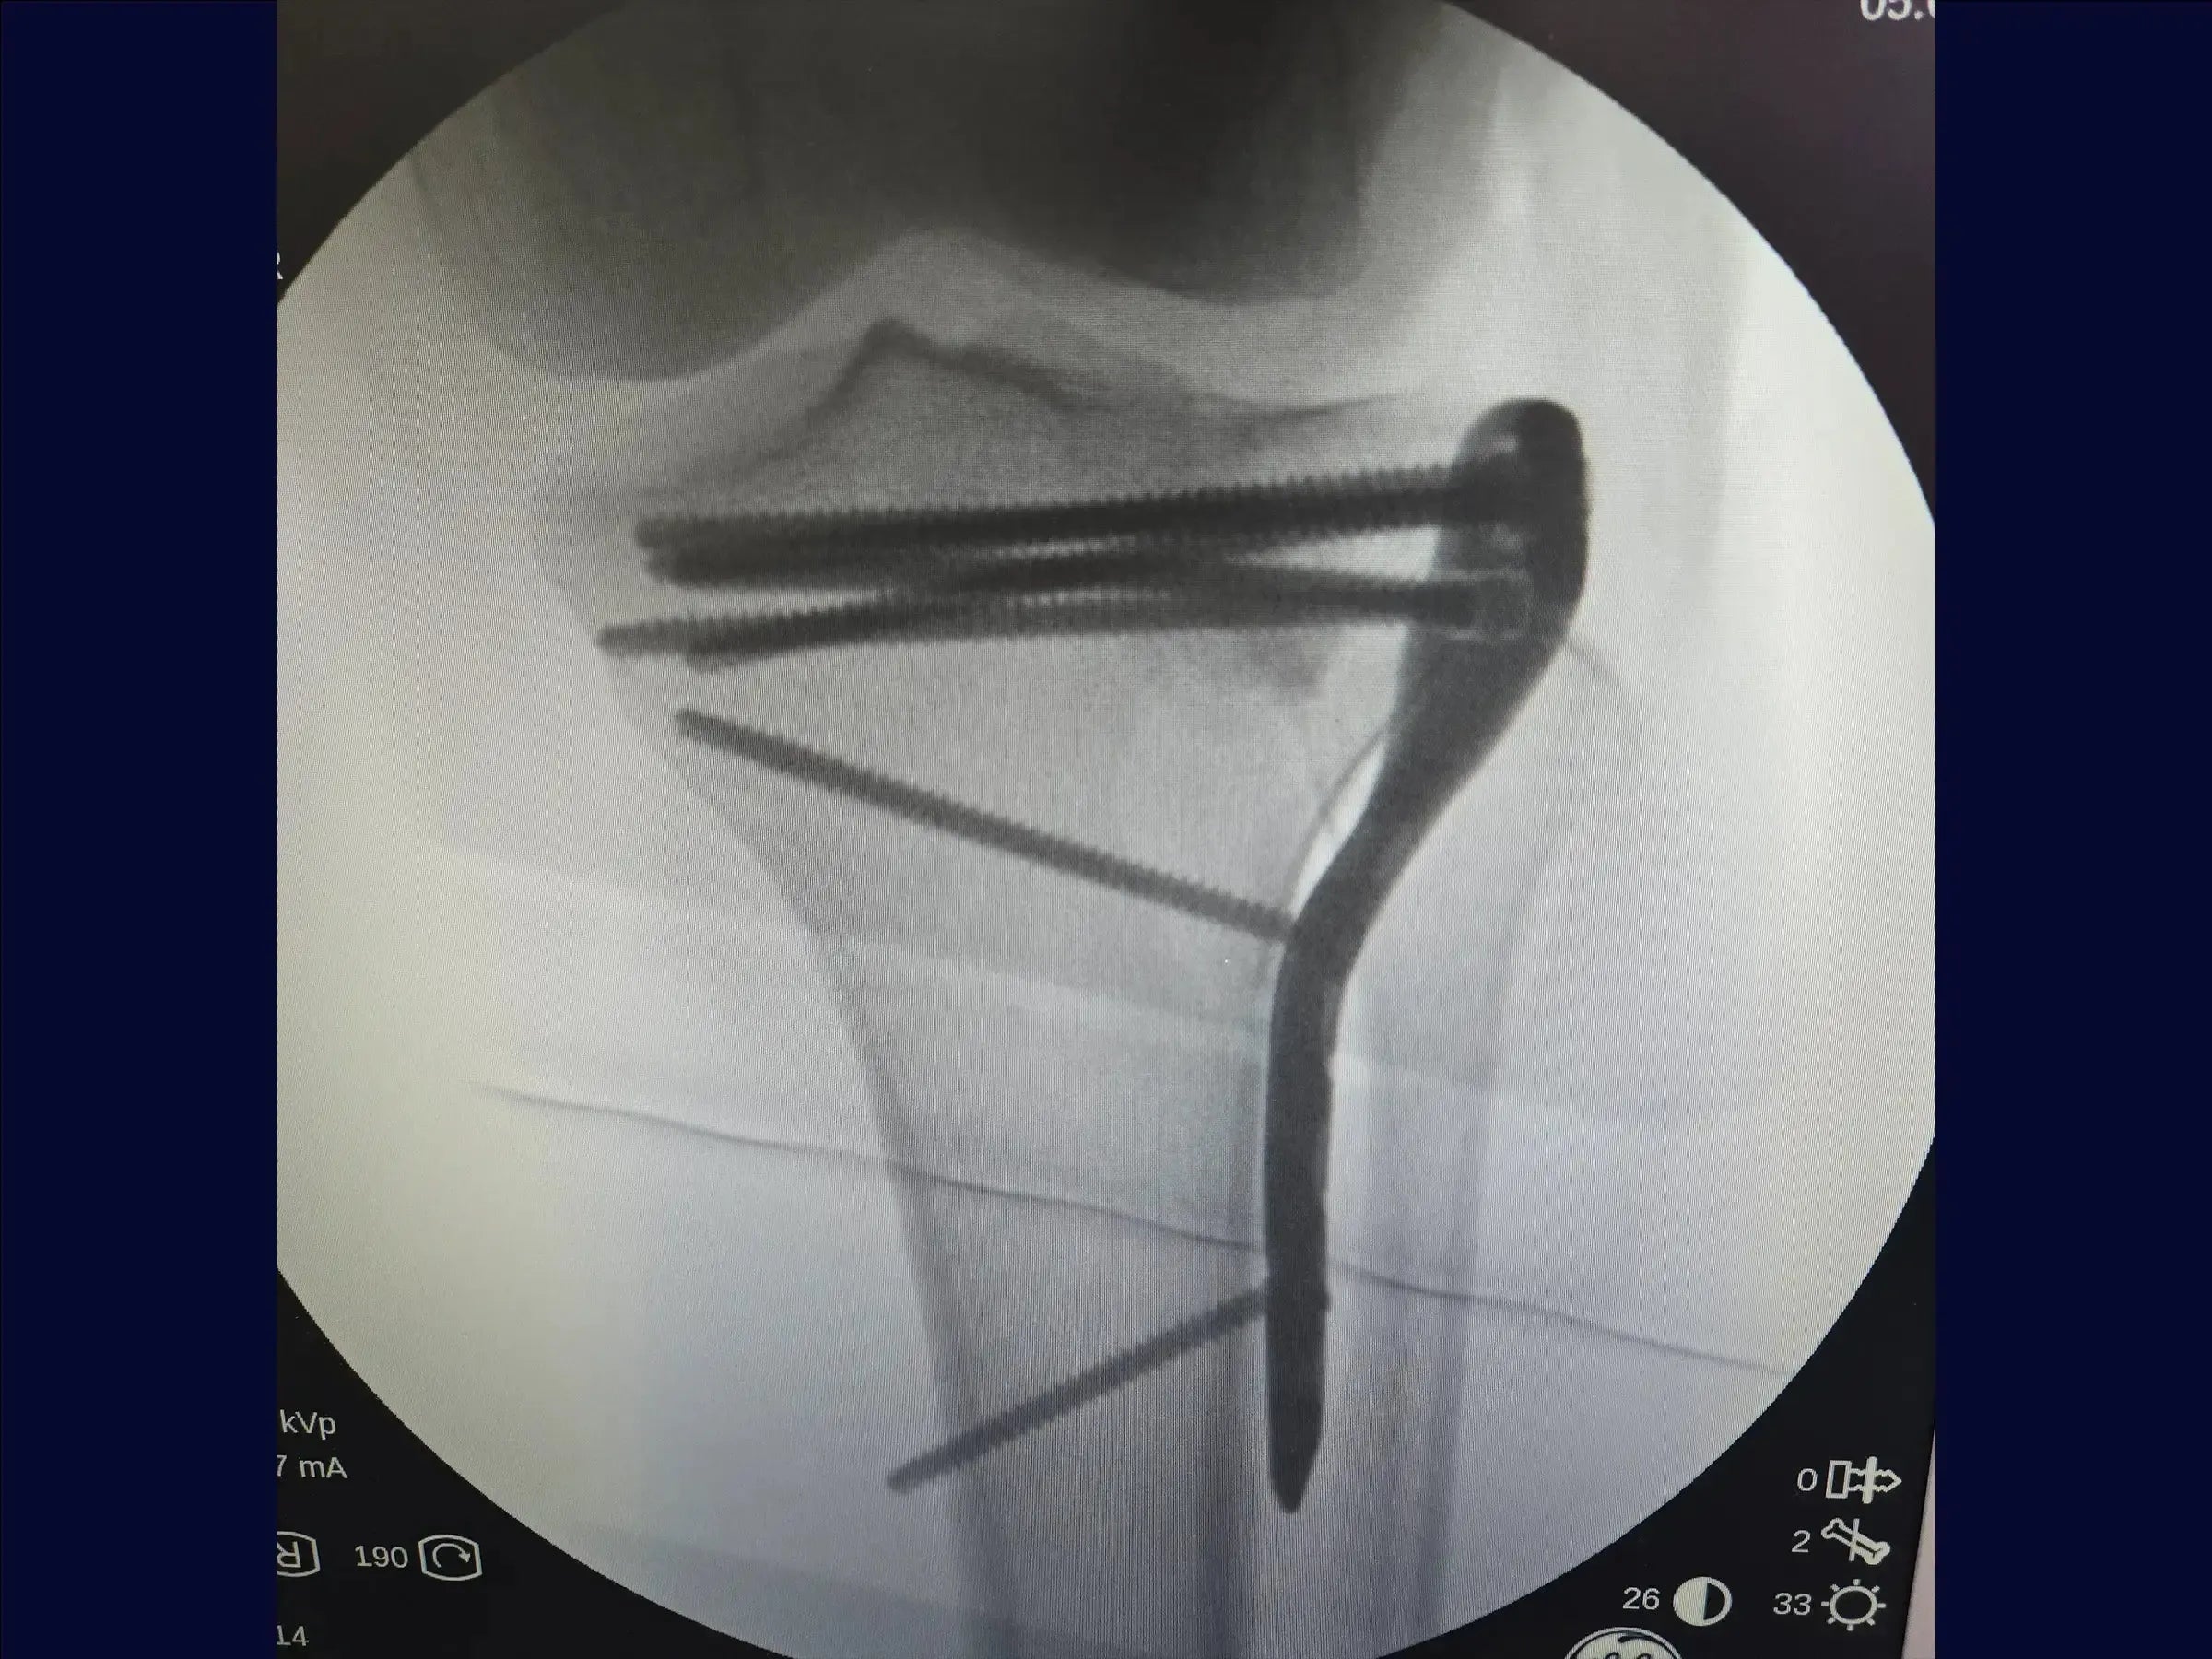

- Fijación con placa y tornillos para reducción y estabilización anatómica.

- Elevación precisa de la depresión: metodología para levantar el bloque óseo impactado de manera uniforme, con sobrecorrección discreta para la acomodación y estabilidad del injerto, utilizando control bimanual.

- Estrategia de Fijación Estable: Aplicación de la placa con tornillo en un punto estratégico para la compresión inicial, seguido de la inserción de tornillos bloqueados subcondrales , formando una red de soporte articular.